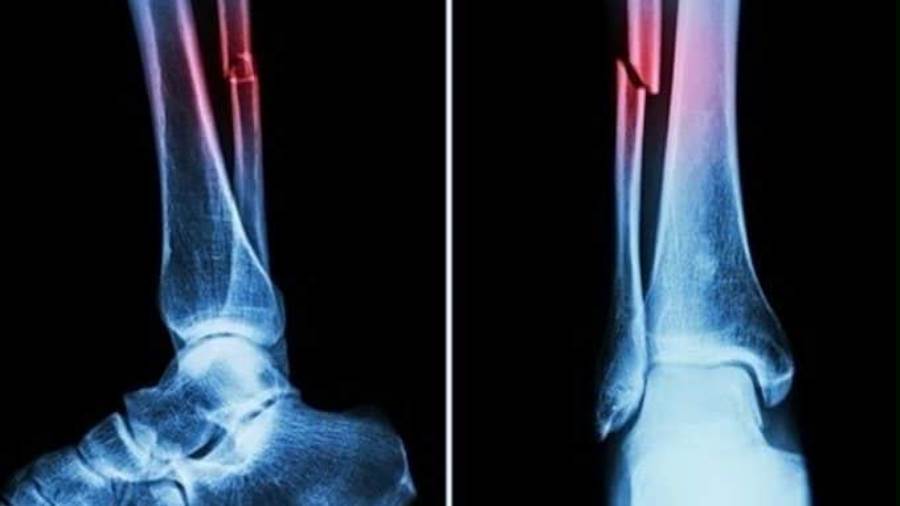

أعلن فريق بحثي في مقاطعة تشجيانج شرقي الصين عن منتج طبي جديد، "غراء عظمي" قادر على علاج الكسور وإعادة ربط شظايا العظام في ثلاث دقائق فقط، في خطوة وصفت بأنها اختراق علمي في عالم جراحة العظام، بحسب قناة "NDTV".

أكدت الاختبارات المعملية أن Bone-02 حقق نتائج جيدة من حيث السلامة والفعالية. في إحدى التجارب، أُجريت العملية في أقل من 180ثانية "ثلاث دقائق"، بينما استغرقت طرق العلاج التقليدية وقتًا طويلاً لزرع الشرائح الفولاذية.

وأظهرت التجارب التي أُجريت على أكثر من 150 مريضًا نتائج ناجحة، مما يزيد من إمكانية استخدامه كبديل للغرسات المعدنية التقليدية المستخدمة لتثبيت العظام. ويقول العلماء إنه قد يقلل أيضًا من خطر العدوى.